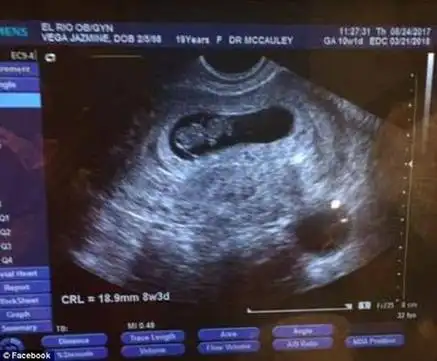

孕妇b超显示"双胞胎" 保胎4月变"单胞胎"